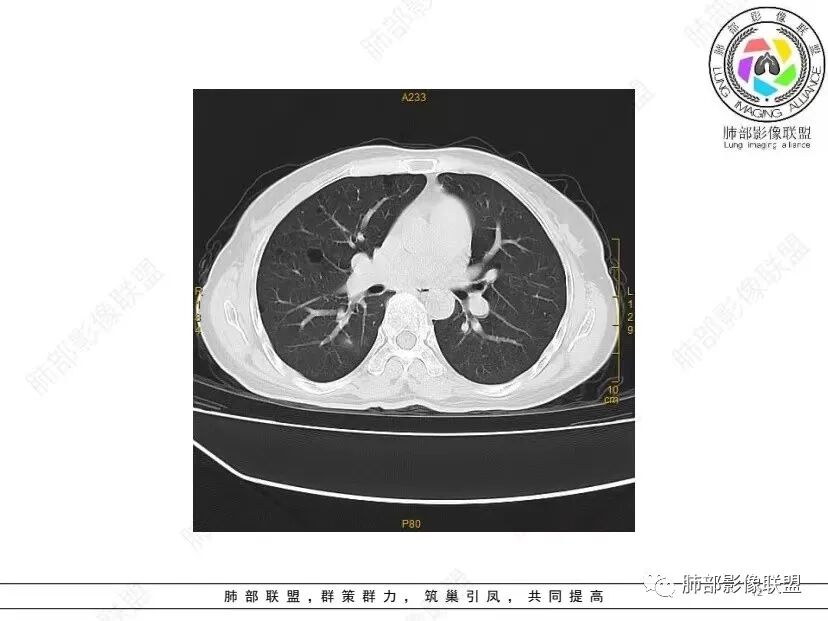

中年女性,否认肿瘤病史,双肺多发气囊,中下肺相对多发,考虑LIP,鉴别BHD综合征。

秦化君: 晨读 双肺不均匀散在多发囊状影,大小不等,部分囊形态欠规整,壁薄均匀,部分囊胸膜下平行。双肺少许斑片状磨玻璃影,边缘模糊。考虑BHD综合征。鉴别PCP,LIP。

红日初升: 中年女性,双肺多发气囊,背景干净,大小不一,下肺韧带旁较大,考虑BHD,鉴别LIP、LAM

玫: 晨读:女,49岁,双肺散在多发囊性病灶影,薄壁,部分层面病灶形态欠规整,右肺下叶少许磨玻璃影,边缘模糊,考虑LIP,鉴别BHD。

宇宙: 中年女性,两肺多发大小不等薄壁囊状影,两肺纵膈胸膜下分布明显,考虑BHD,鉴别LAM

放射线 (王秀仙): 双肺多发囊状影,大小不等,部分囊壁呈磨玻璃样,另双肺见斑片状磨玻璃影,边缘模糊。女性,考虑LIP,鉴别BHD

段建民: 双肺多发囊状影,多成圆形或三角形,囊壁薄且均匀,正常肺野内透过度尚可。双肺多发囊状影的鉴别,中心肺气肿,间隔旁肺气肿,PJP,支气管扩张,囊肿,支气管肺发育异常;LAM LIP PLCH BHD;囊腔腺癌,转移瘤,血播金葡菌……

本病例首先考虑BHD。

良孑: 两肺多发含气囊腔,大小不等,囊周见血管伴行,首选BHD,建议查双肾情况,鉴别Lam

这个病例目前影像特点,多囊,囊主要位于下肺,胸膜下及小叶核心为主

伴随少许索条,而且这些病灶与囊不一定有相关性

囊的分布,PLCH基本可以排除

囊壁薄且均匀,光滑,形态规则,基本除外恶性

单纯囊,无斑片及其他实性病灶,感染不支持,可能的是:LAM、BHD、LIP

从囊的分布、大小,BHD可能性可能大一些,但是LIP、LAM都可以这样表现,具体诊断应该是这三种之一,影像缩小到这里我觉得就差不多了,结合临床考虑就行,不支持靠影像强下结论。